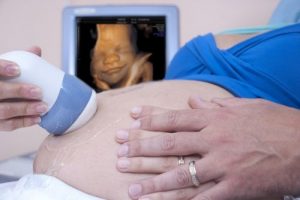

En kvinne vet at hun er en mor på sin første ultralyd. Hun kan ikke holde tårene tilbake når hun hører barnets raske hjerteslag. Hennes eget hjerte slår like raskt. Hun blir overveldet av glede over denne første kontakten med sitt ufødte barn.

Den engstelige moren drømmer om den dagen hun får holde sin lille solstråle i armene for første gang. Hun vet at de er knyttet sammen for resten av livet. Hver ultralyd, hver lille bevegelse, blir en milepæl i morens liv.